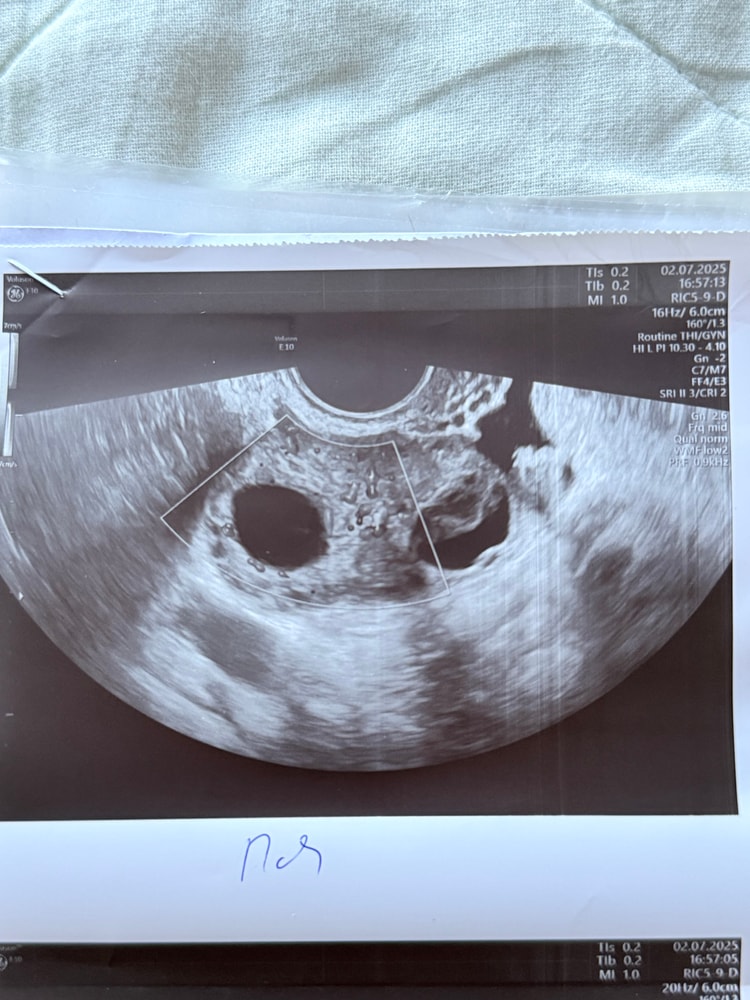

На 16 ДЦ (23 июня) - фолликул 18.6. Сделала укол ХГЧ 10000.На 25 ДЦ (2 июля) была на УЗИ, врач не поняла была ли О. Но была жидкость в МТ 15 мм. Предполагаю что О была на 18 ДЦ (25 июня). С 19 ДЦ начала пить Дюфастон. Цикл 27 дней (на Дюфастоне) Сегодня первый день задержки, обычно месячные начинаются прямо утром.

Это фолликулы (слева 23 мм, справа 17 мм (вырос после укола ХГЧ))